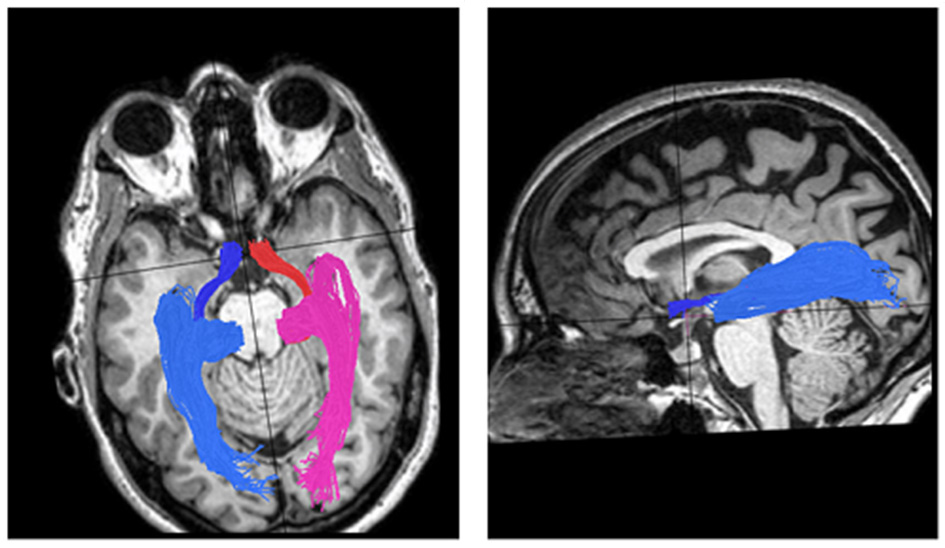

Tracking white matter is done using Diffusion Tensor Imaging (DTI). The method is based on diffusion, the random motion of water molecules in the extra- and intra-cellular spaces. When the motion of molecules is limited by tubular structures such as the axons, diffusion will be mainly along the direction of the axonal bundle, rather than in the perpendicular plane (anisotropic diffusion). Using this method, information regarding localization and directionality of the fibers as well as evaluation of the quality of their cohesiveness and their ability to conduct the neuronal signal can be obtained (Basser et al., 1994; Mori et al., 1999). Figure 3 demonstrates reconstruction of the visual pathways using DTI and fiber tractography, and shows the optic tract that connects the optic chiasm to the LGN, creating a rather thin and compact fiber bundle; and the optic radiation that connects the LGN to the occipital cortex containing its anterior segment, the Meyer's loop.

Figure 3

DTI visual pathways fiber groups superimposed on T1 images. Left: axial view of the optic tracts and radiations in one control subject. The optic tracts, which connect the optic chiasm to the LGN, are colored red for the right side and blue for the left side. The right and left optic radiations, which connect the LGN to the calcarine cortex, are colored pink for right and light blue for left. Right: sagital view of the left optic tract and radiation.